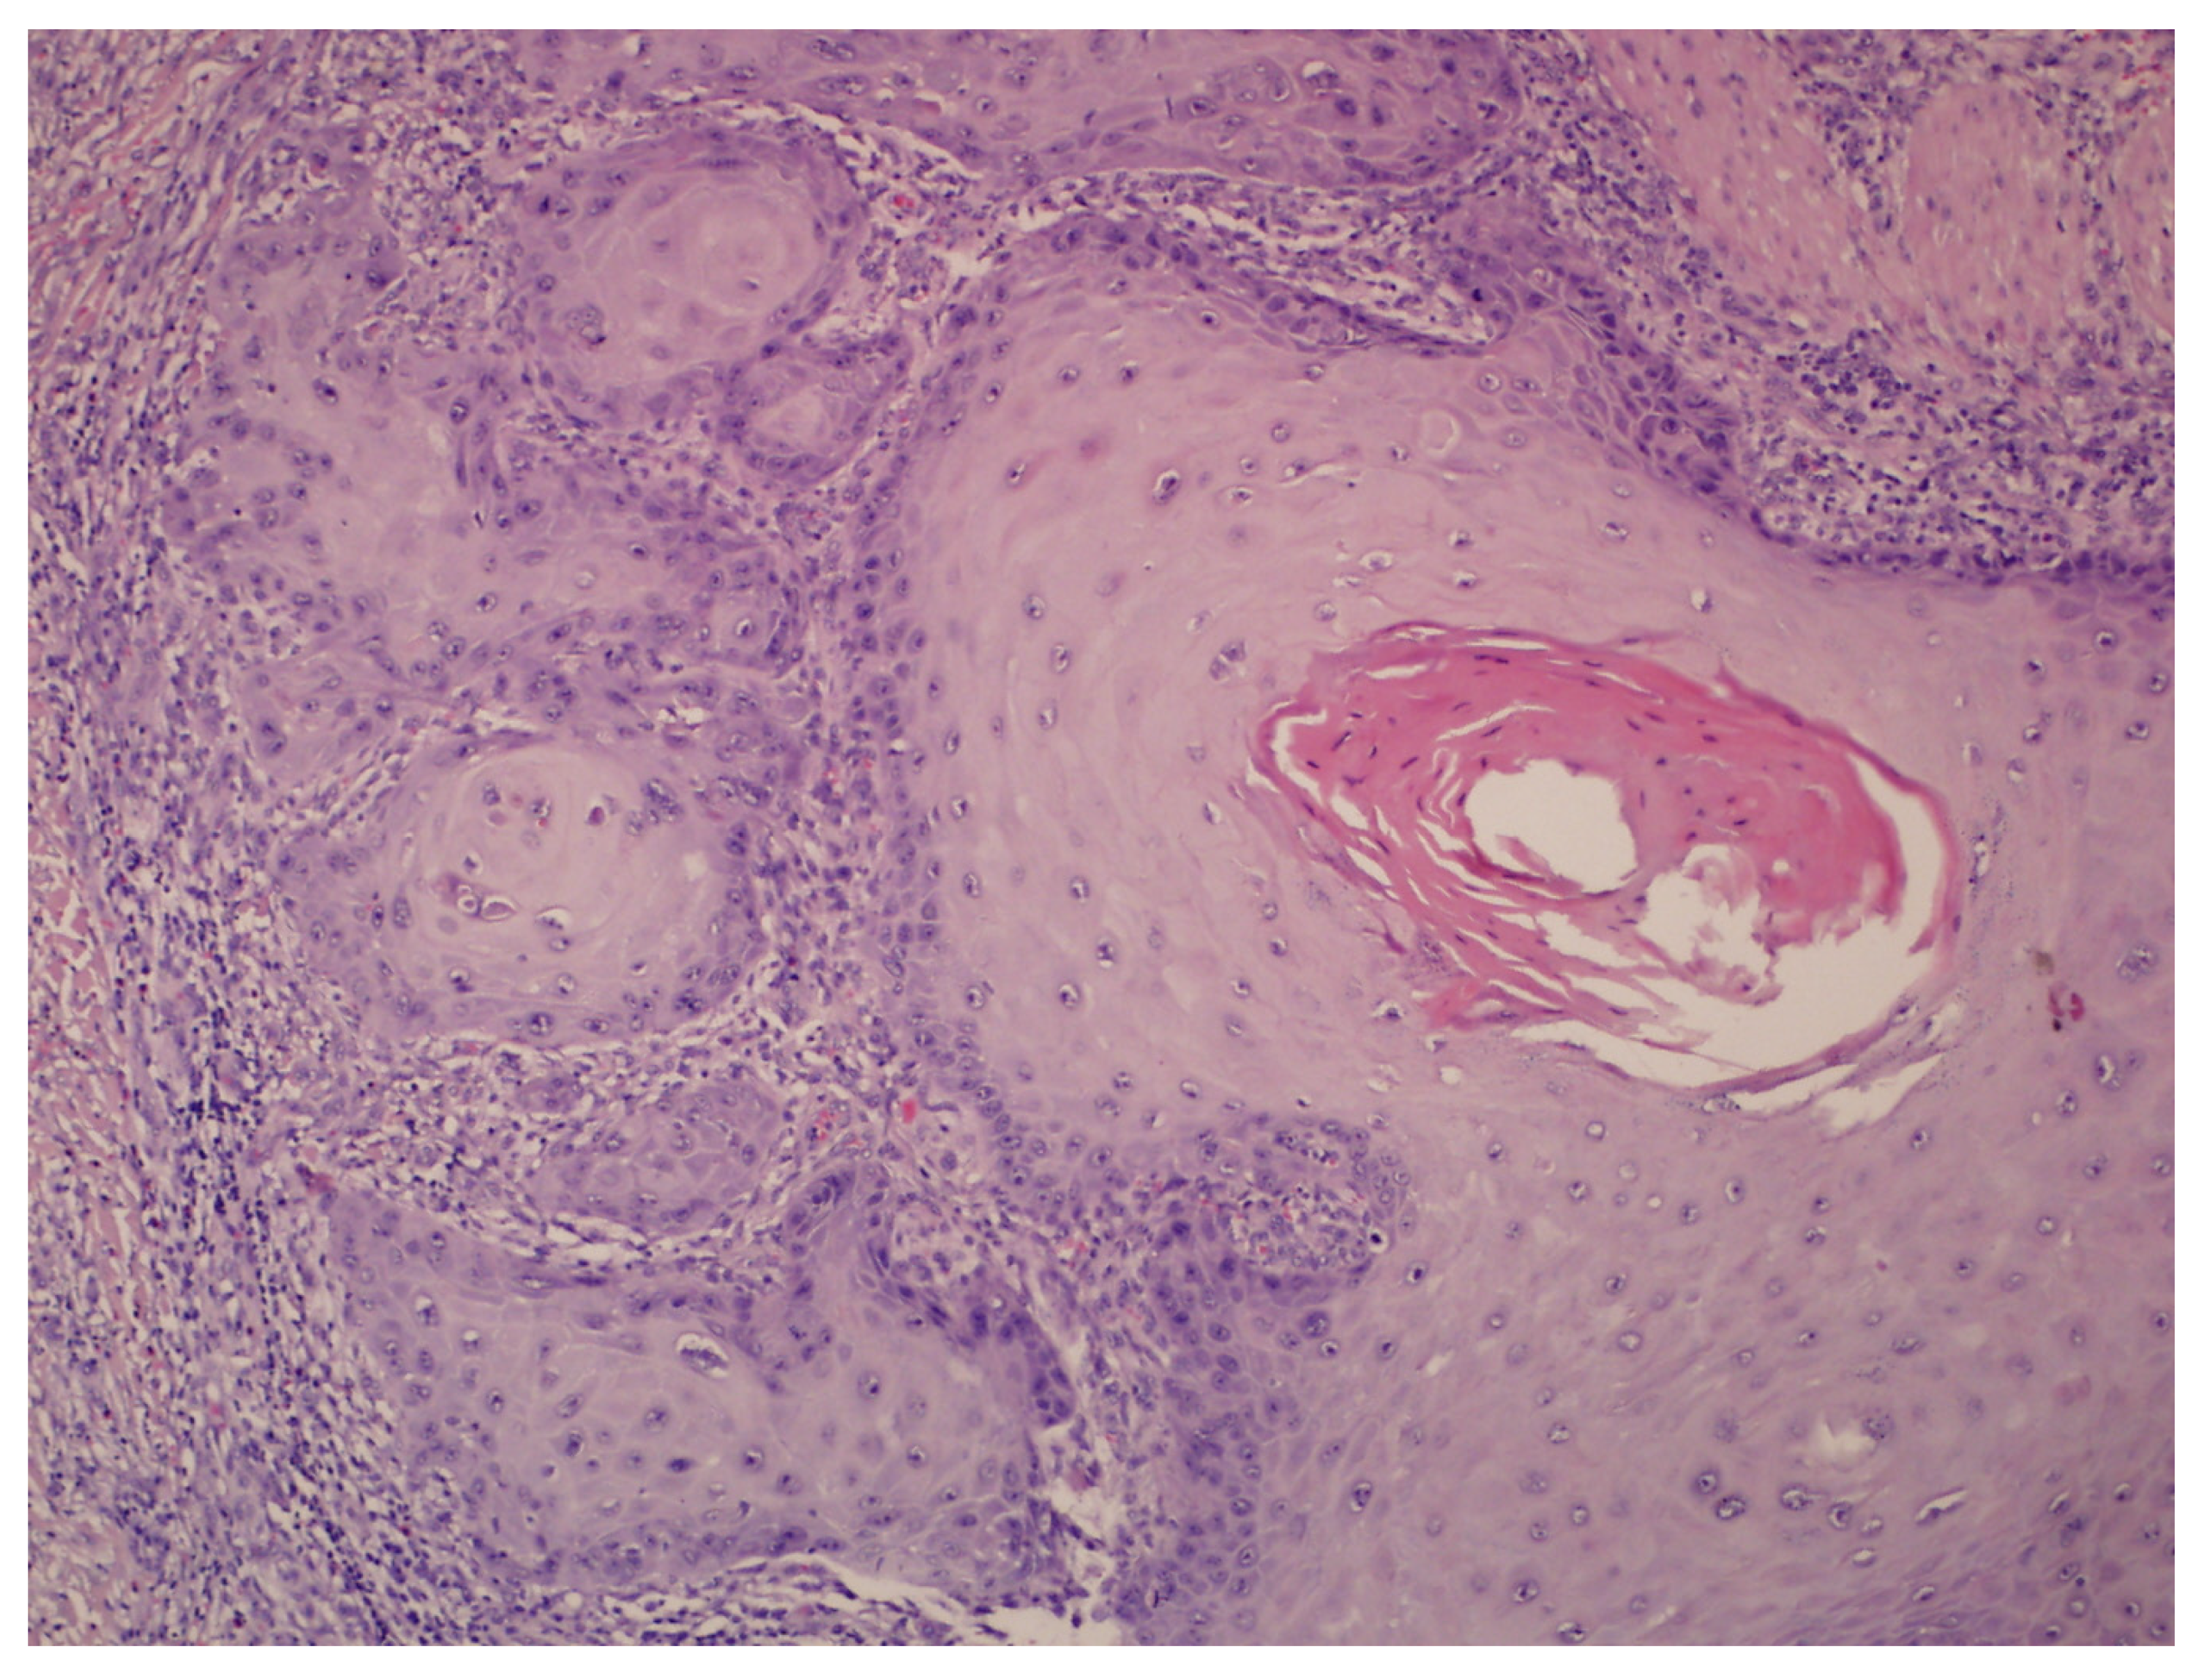

- Hyperkeratosis, papillomatosis, and acanthosis;

- Broad, blunt-ended rete ridges with a characteristic “bulldozing” architectural pattern;

- Minimal cellular atypia, though pleomorphic changes and eosinophilic cytoplasm may be observed, differentiating EC from common warts and conventional SCC.